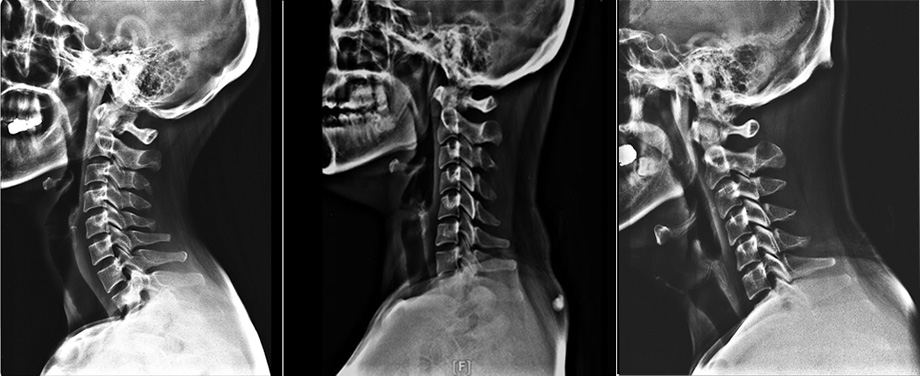

2. 거북목증후군을 확인할 수 있는 가장 쉬운 검사는 X-ray 검사다.

• 정상목

• 일자목

• 거북목

거북목이 있으면 목 뒤가 자주 뻐근한 통증이 자주 발생합니다. 이런 증상이 지속적으로 나타난다면 X-ray 검사를 한번 받아보는 것이 좋습니다. X-ray는 비용적으로도 부담이 없고, 검사 시간도 매우 짧기 때문에 X-ray 검사를 통해 전반적인 목의 상태를 확인해보는 것이 목 건강에 도움이 됩니다. X-ray 검사를 통해 목뼈의 전체적인 배열을 보고 일자목이나 거북목증후군, 역C자형 목 등을 알 수 있습니다. 목뼈가 C자형의 곡선 형태가 아닌 일자 형태로 변형되어 있으면 일자목, 그보다 더 앞으로 돌출되었으면 거북목이라 볼 수 있습니다.